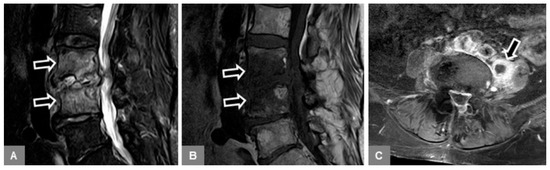

3.2. Vertebral Endplate Contour